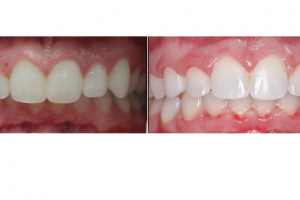

Posted by Lenk Orthodontics on Thursday, January 28, 2021 Lenk Orthodontics isn’t just about teeth: OUR FOCUS IS THE SMILE, BITE, AND OVERALL ESTHETICS…. LOOK AT THE DIFFERENECES IN THIS …

Proud to be a reason this girl’s smile is so bright. Can’t wait to see her pops without braces in a month or so !!! Posted by Lenk Orthodontics …